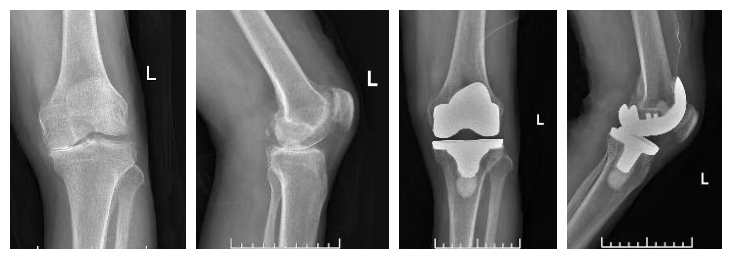

膝关节置换手术